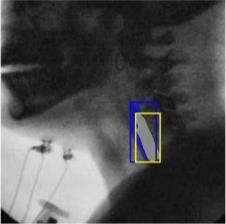

The videofluoroscopic swallowing study (VFSS) is a gold-standard imaging technique for assessing swallowing, but analysis and rating of VFSS recordings is time consuming and requires specialized training and expertise. Researchers have recently demonstrated that it is possible to automatically detect the pharyngeal phase of swallowing and to localize the bolus in VFSS recordings via computer vision, fostering the development of novel techniques for automatic VFSS analysis. However, training of algorithms to perform these tasks requires large amounts of annotated data that are seldom available. We demonstrate that the challenges of pharyngeal phase detection and bolus localization can be solved together using a single approach. We propose a deep-learning framework that jointly tackles pharyngeal phase detection and bolus localization in a weakly-supervised manner, requiring only the initial and final frames of the pharyngeal phase as ground truth annotations for the training. Our approach stems from the observation that bolus presence in the pharynx is the most prominent visual feature upon which to infer whether individual VFSS frames belong to the pharyngeal phase. We conducted extensive experiments with multiple convolutional neural networks (CNNs) on a dataset of 1245 bolus-level clips from 59 healthy subjects. We demonstrated that the pharyngeal phase can be detected with an F1-score higher than 0.9. Moreover, by processing the class activation maps of the CNNs, we were able to localize the bolus with promising results, obtaining correlations with ground truth trajectories higher than 0.9, without any manual annotations of bolus location used for training purposes. Once validated on a larger sample of participants with swallowing disorders, our framework will pave the way for the development of intelligent tools for VFSS analysis to support clinicians in swallowing assessment.